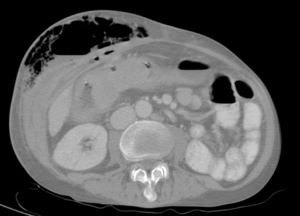

| Abdominal CT with right colocutaneous fistula and associated subcutaneous emphysema. | |